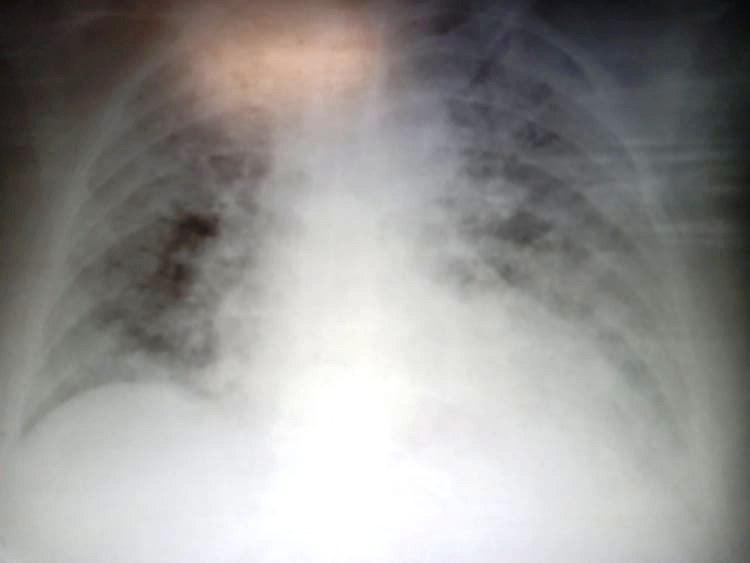

Αυτή είναι η ακτινογραφία μιας ασθενούς, 60 ετών, που έπαιρνε μόνο ένα χάπι για τον θυρεοειδή. μπήκε με ανάγκες οξυγόνου στα 4lt και μέσα σε 4 μέρες έφτασε στα 90lt και διασωληνώθηκε.

Όταν μας ρωτάτε λοιπόν “τι έπαθε γιατρέ, αφού ήταν καλά”…

ε, αυτό έπαθε.